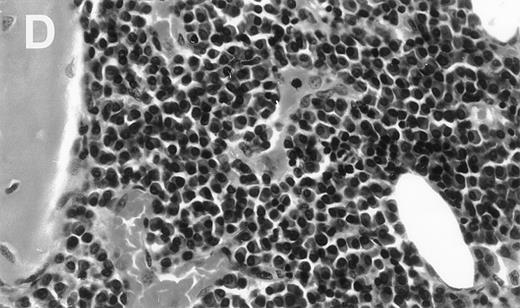

Human Ig levels (A through C ) and histology of decalcified human bone sections ( D through F ) from SCID-hu hosts inoculated with bone marrow cells ( A and D ), purified plasma cells ( B and E ), and PC-depleted bone marrow cells ( C and F ) from patient no. 2. Inserts demonstrate CD38/CD45 fluorescent profiles and sort windows of cells used for each host.